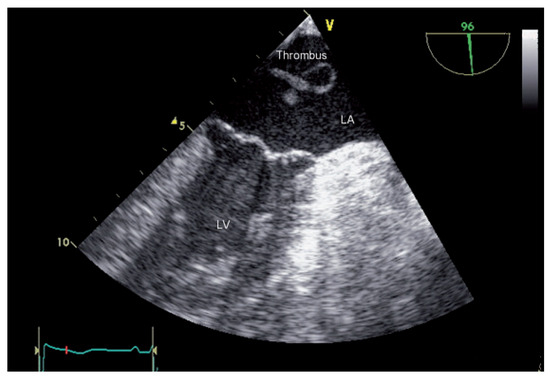

Trapped Thrombus in the Open Foramen Ovale